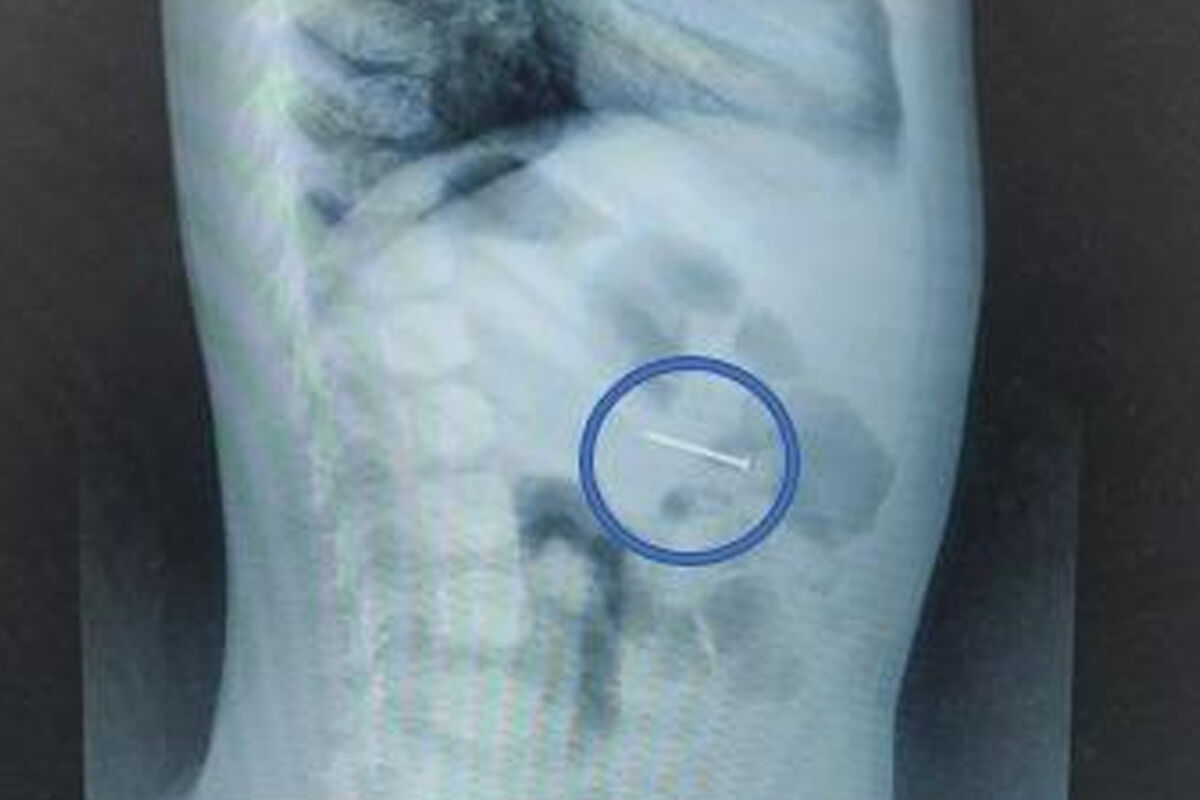

Врачи Детского клинического центра имени Л.М. Рошаля спасли четырехлетнего мальчика, который проглотил гвоздь. Об этом сообщили в пресс-службе минздрава Московской области.

При поступлении ребенка в больницу его мать рассказала, что сын проглотил гвоздь, который нашел дома: женщина пояснила, что у них в квартире идет ремонт. Сам момент проглатывания инородного предмета она не видела, но после ребенок начал кашлять, а в слюне появились следы крови.

Обследование подтвердило версию родительницы.

«Своевременно начатое вмешательство помогло избежать серьезных последствий. Сперва мы сделали рентгенографию – она подтвердила наличие гвоздя в желудке, а после выполнили гастроскопию: с помощью эндоскопических щипцов аккуратно захватили гвоздь за острый конец и извлекли его через ротовую полость», — поделился врач-эндоскопист Руслан Мусаев, добавив, что манипуляция заняла около 20 минут.

После этого мальчик еще несколько часов находился под наблюдением врачей. В тот же день его выписали домой.